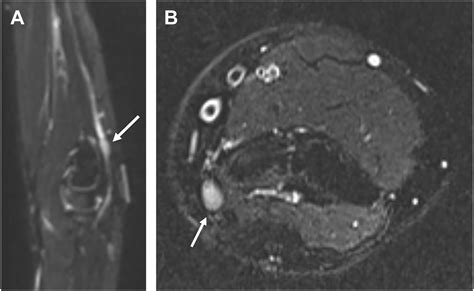

To overcome this, this specialized imaging employs specific pulse sequences designed to suppress the signal from fat—which often obscures nerve detail—while enhancing the signal from water-rich tissues like nerves. This process effectively makes the nerves "light up" on the resulting images, allowing radiologists to assess their anatomy, signal intensity, and trajectory in high detail.

Once the images are acquired, they are analyzed by a radiologist with specialized expertise in musculoskeletal or neuroradiology. The goal is to identify changes in the nerve's appearance. For instance, a healthy nerve typically appears as a thin, uniform structure with a consistent signal. In contrast, an injured or compressed nerve may exhibit:

• Increased signal intensity: Often indicative of edema (swelling) or inflammation within the nerve.

• Nerve enlargement (fascicular thickening): A sign that the nerve is being subjected to chronic pressure or trauma.